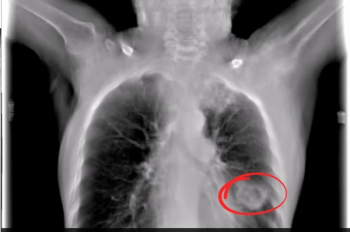

A CT-based radiomic model offered over 10 percent higher specificity and positive predictive value for high-risk lung adenocarcinoma in comparison to a radiographic model, according to external validation testing in a recent study.